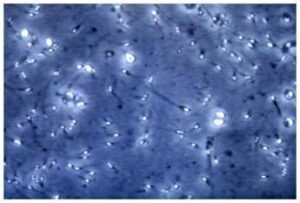

(Adnkronos) - Social 'cattivi maestri' quando parlano di salute. "I consigli medici parziali o fuorvianti condivisi dagli influencer possono causare d...